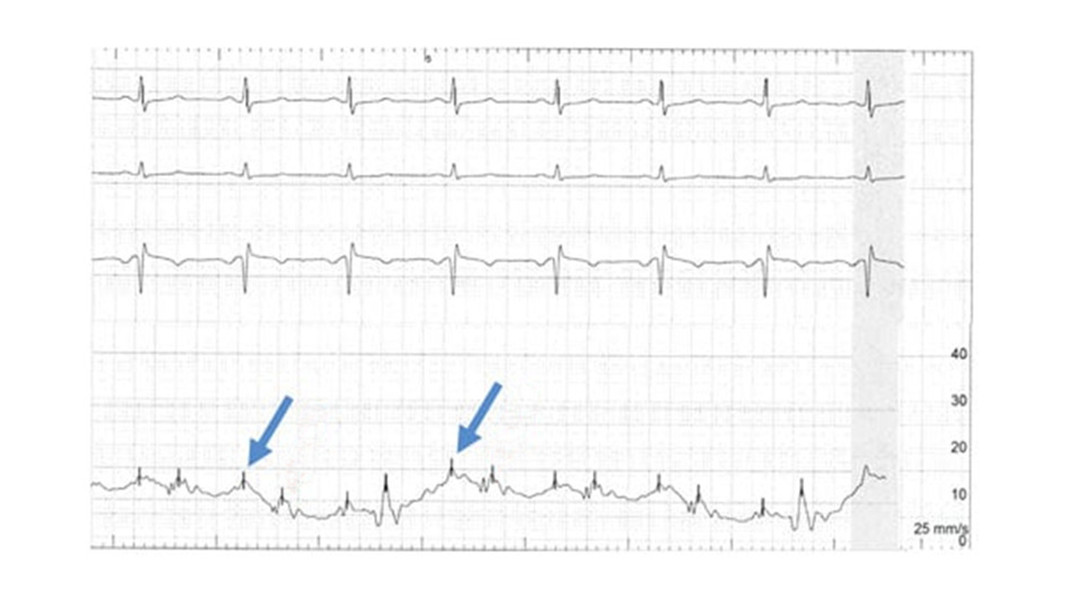

Zapis EKG widoczny na rycinie przedstawia: